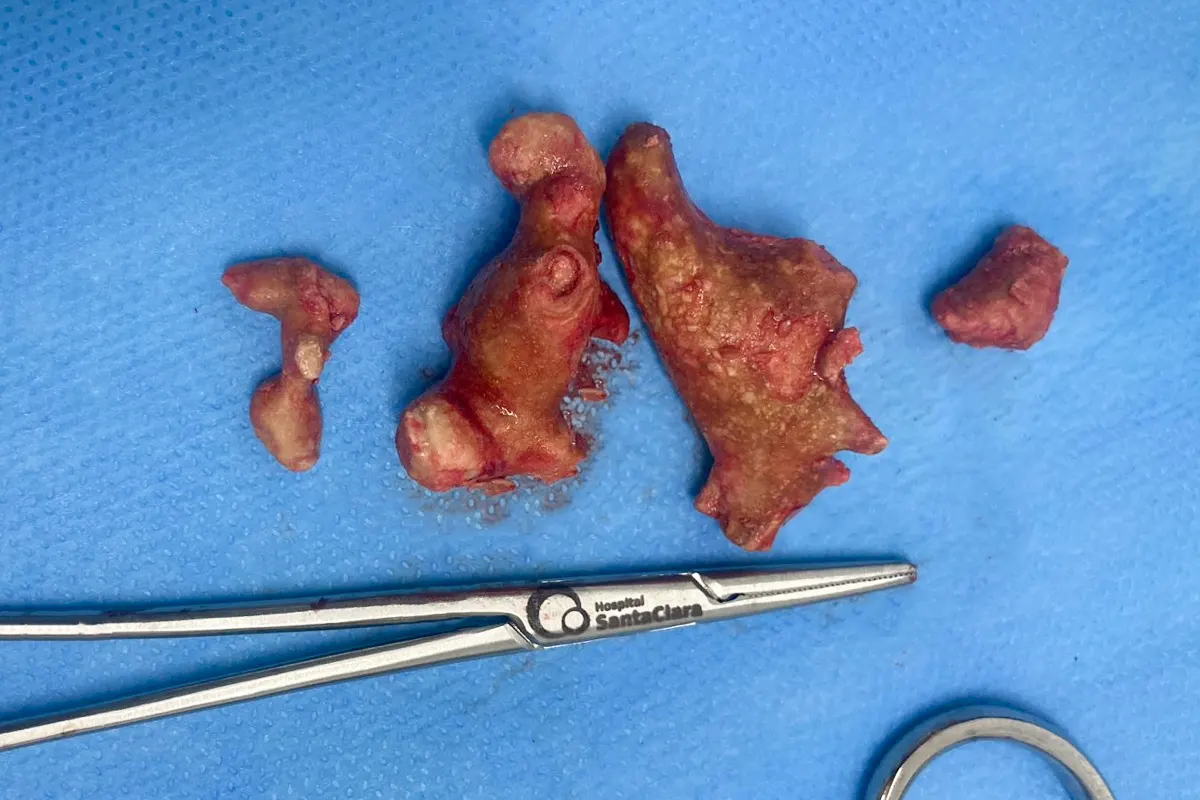

A imagem que ilustra este artigo é real, e os cálculos renais (ou ‘pedras’) retirados do paciente eram de grande porte, como se pode ver ao lado da pinça cirúrgica.